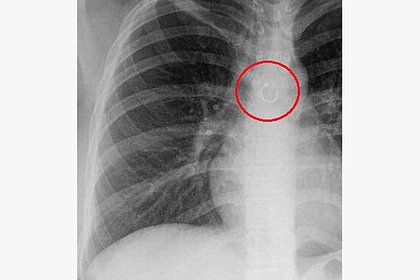

Жительница Мексики Моника Деянира Кабрера Барахас случайно вдохнула пирсинг из носа и проходила так несколько месяцев. Об этом пишет Need To Know.

26-летняя девушка рассказала, что внезапно стала страдать от постоянного кашля. Сначала она списала его на изменение погоды в ее родном штате Нуэво-Леон, но спустя месяц все же обратилась к врачу. Во время обследования в легком Барахас нашли металлическое кольцо — пирсинг из ее носа.

Барахас предположила, что однажды ночью шарик, удерживающий кольцо, раскрутился, и она вдохнула пирсинг во сне. На утро она, скорее всего, решила, что сняла его и куда-то положила, поэтому и не стала паниковать.

Пирсинг удалили из легкого девушки хирургическим путем. Врачам потребовалось две операции, чтобы добраться до него. Оказалось, что кольцо находилось в 0,5 миллиметра от аорты и могло пробить ее

Это было бы смертельно.